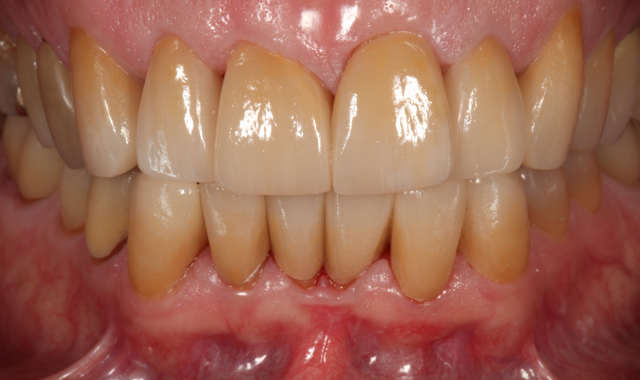

Two weeks after the patient approved the provisionals, the definitive crowns were placed, and the patient was thrilled with the outcome (Figs. 15 and 16).

Fig. 15

Fig. 16